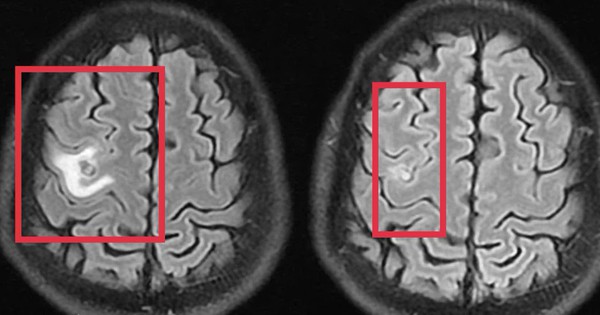

Co giật do sán não suýt nhầm lẫn với u não

(NLĐO) - Tổn thương não do sán khiến bệnh nhân co giật, đau đầu nhẹ - triệu chứng mờ nhạt nhưng dễ bị bỏ sót.